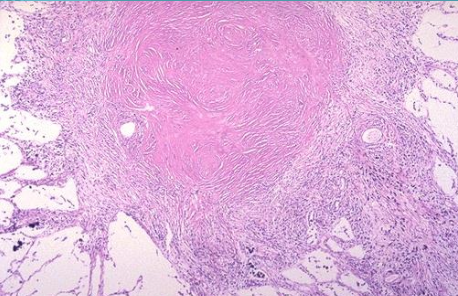

Qué es

Silicosis

Silicosis microscópicamente

Área central de fibras de colágeno arremolinada con una zona más periférica de macrófagos cargados de polvo